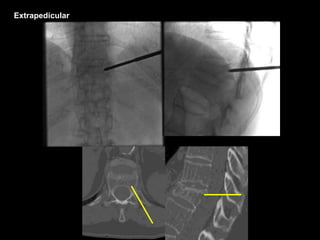

Extrapedicular

Biopsy

Oblique View